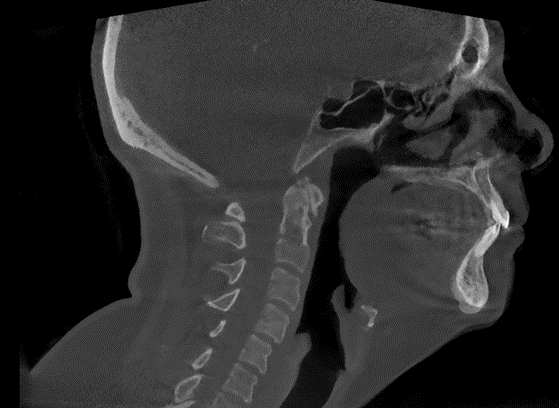

The upper cervical spine, especially the atlas (C1) and axis (C2), sits just beneath the brainstem. It’s a highly sensitive and mobile area, where even the smallest misalignment can affect the nervous system. That’s why accuracy matters so much. With CBCT, we can see the neck and skull in 3D, allowing our doctors to measure the exact angle and position of these bones.

So, how CBCT imaging enhances upper cervical precision comes down to this: clarity. Regular X-rays offer a flat, two-dimensional view that can hide subtle but clinically significant issues. CBCT, on the other hand, gives us detailed cross-sections from multiple angles—helping us find exactly where the problem is and how best to correct it.

At Neuro St Pete, this technology helps us design more accurate and gentle adjustments. No guessing. No cracking. Just precise corrections that are custom-tailored to your anatomy. And when the correction is right, it holds longer, giving your body time to heal without repeated interventions.

Patients from St Petersburg, Gulfport, and Clearwater often tell us they’re relieved to finally have clear imaging that explains their symptoms. It’s not uncommon for someone to walk in with years of misdiagnosed pain, only to find that a small misalignment near the brainstem was the missing link. That’s how CBCT imaging enhances upper cervical precision—by bringing invisible issues into focus.